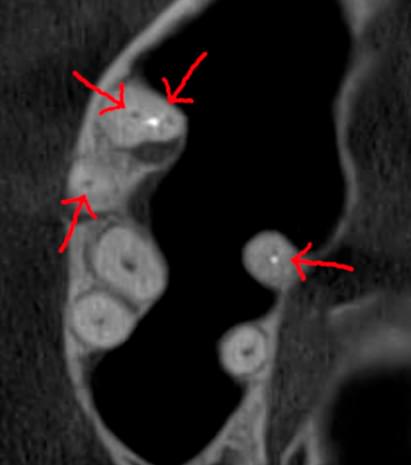

При плануванні імплантації лікарю важливо знати дві речі: об'єм кістки та точне розташування нервів.

КТ дозволяє провести віртуальну операцію: встановити імплант у програмі, виключивши будь-які ризики травмування пацієнта.